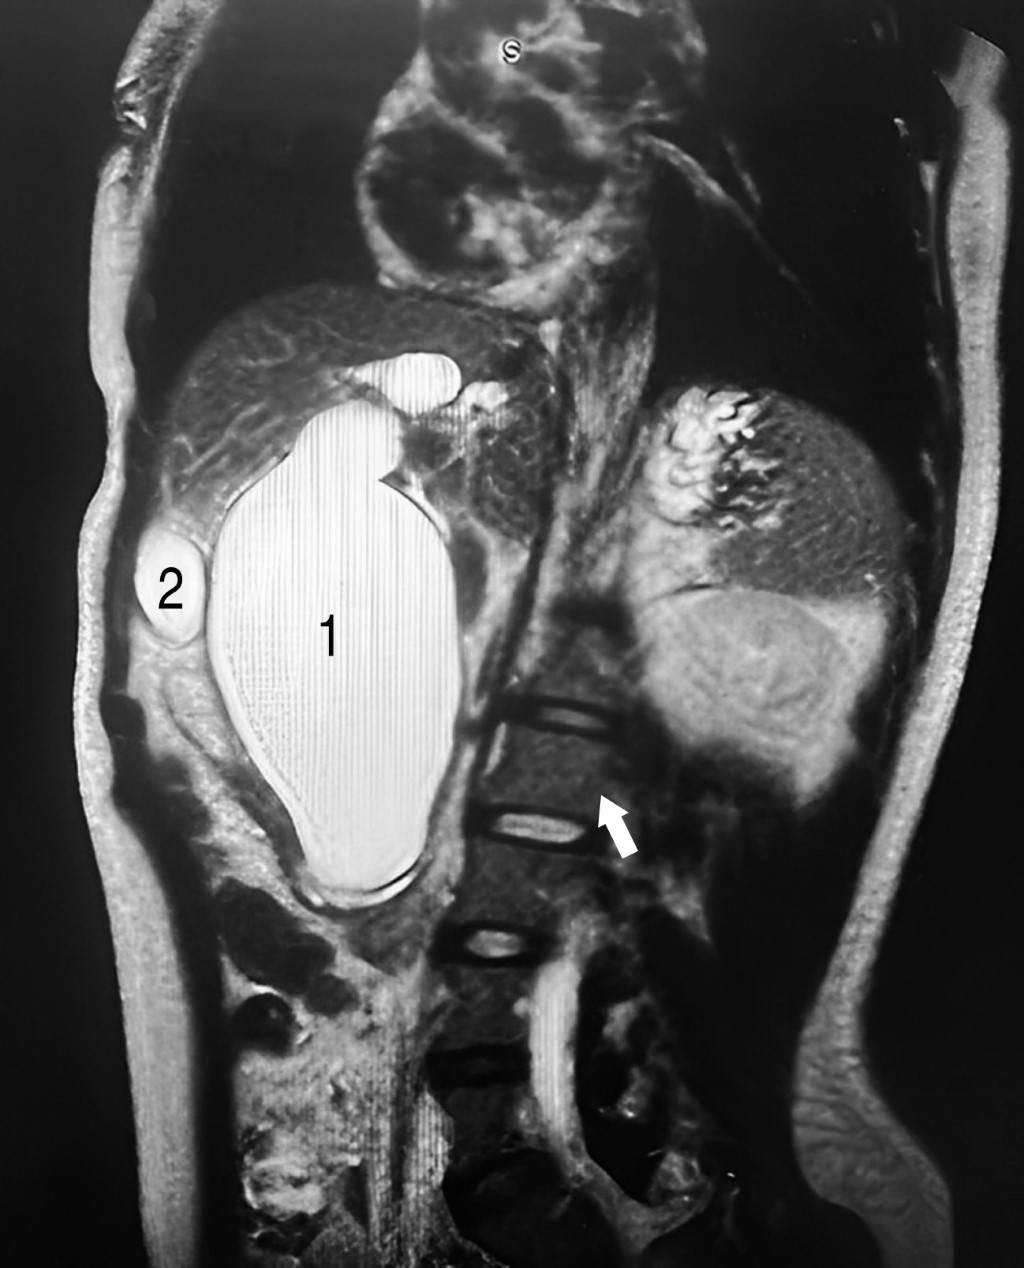

In her home, a hepatic and biliary tract ultrasound (HBVUS) was performed to interpret the presence of a hepatic cyst. Later, an M-RC was performed in Pachuca, Hidalgo, which confirmed the general surgeon's diagnosis of a common bile duct cyst. Due to a lack of resources, the surgeon referred her to the HCGFAA. Laboratory tests were performed (Table 1), and a new CR-M was performed (Figures 3 and 4), which showed a modified QC-IVA-Todani cyst (Figure 2).

Findings: an atrophic gallbladder without the presence of gallstones, a 7.6 mm cyst in the cystic duct, saccular dilatation of the intrahepatic and extrahepatic bile duct with a diameter of 18 mm in the right hepatic, 15 mm in the left hepatic duct and a confluence zone of 33 mm (carina) was seen. A maximum dilatation of the common bile duct of 70 mm, distal common bile duct of 23 mm, and the duct of Wirsung with normal dimensions were observed.